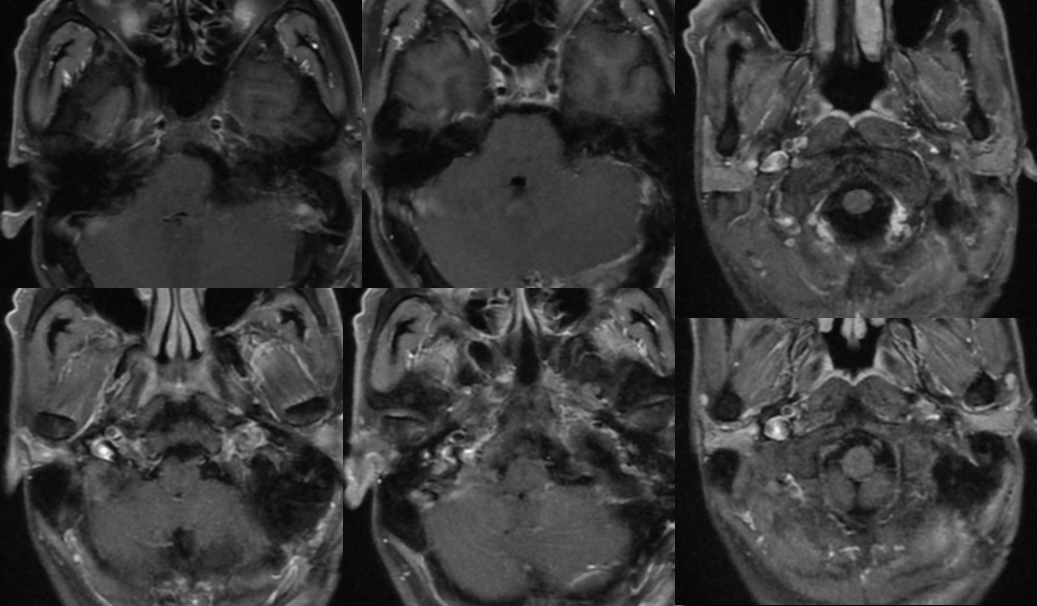

术前影像

![]()